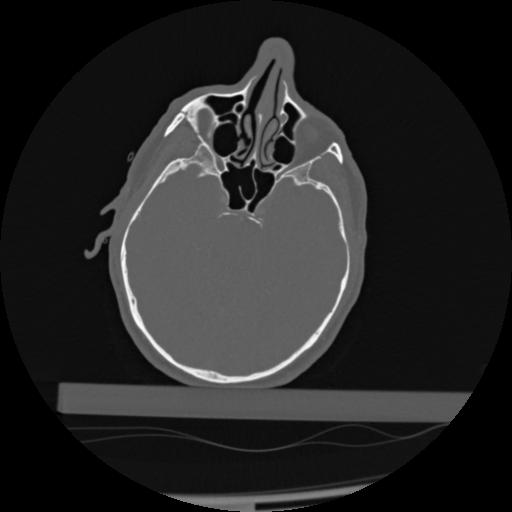

22 ANGIO,CE,Vol,0.5,ANGIO,,